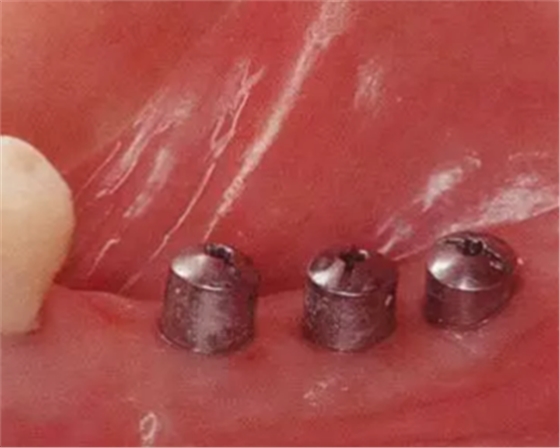

▲圖10-1,2

圖10-1 頰側和牙槽嵴有角化齦的存在,但是愈合期間內覆蓋螺絲露出(Type3-Class2)

▲圖10-3,4

圖10-3 第二次手術前的(牙合)面照。

圖10-4 為了在頰側、舌側進行FGG,在上頜腭側采集大塊移植片